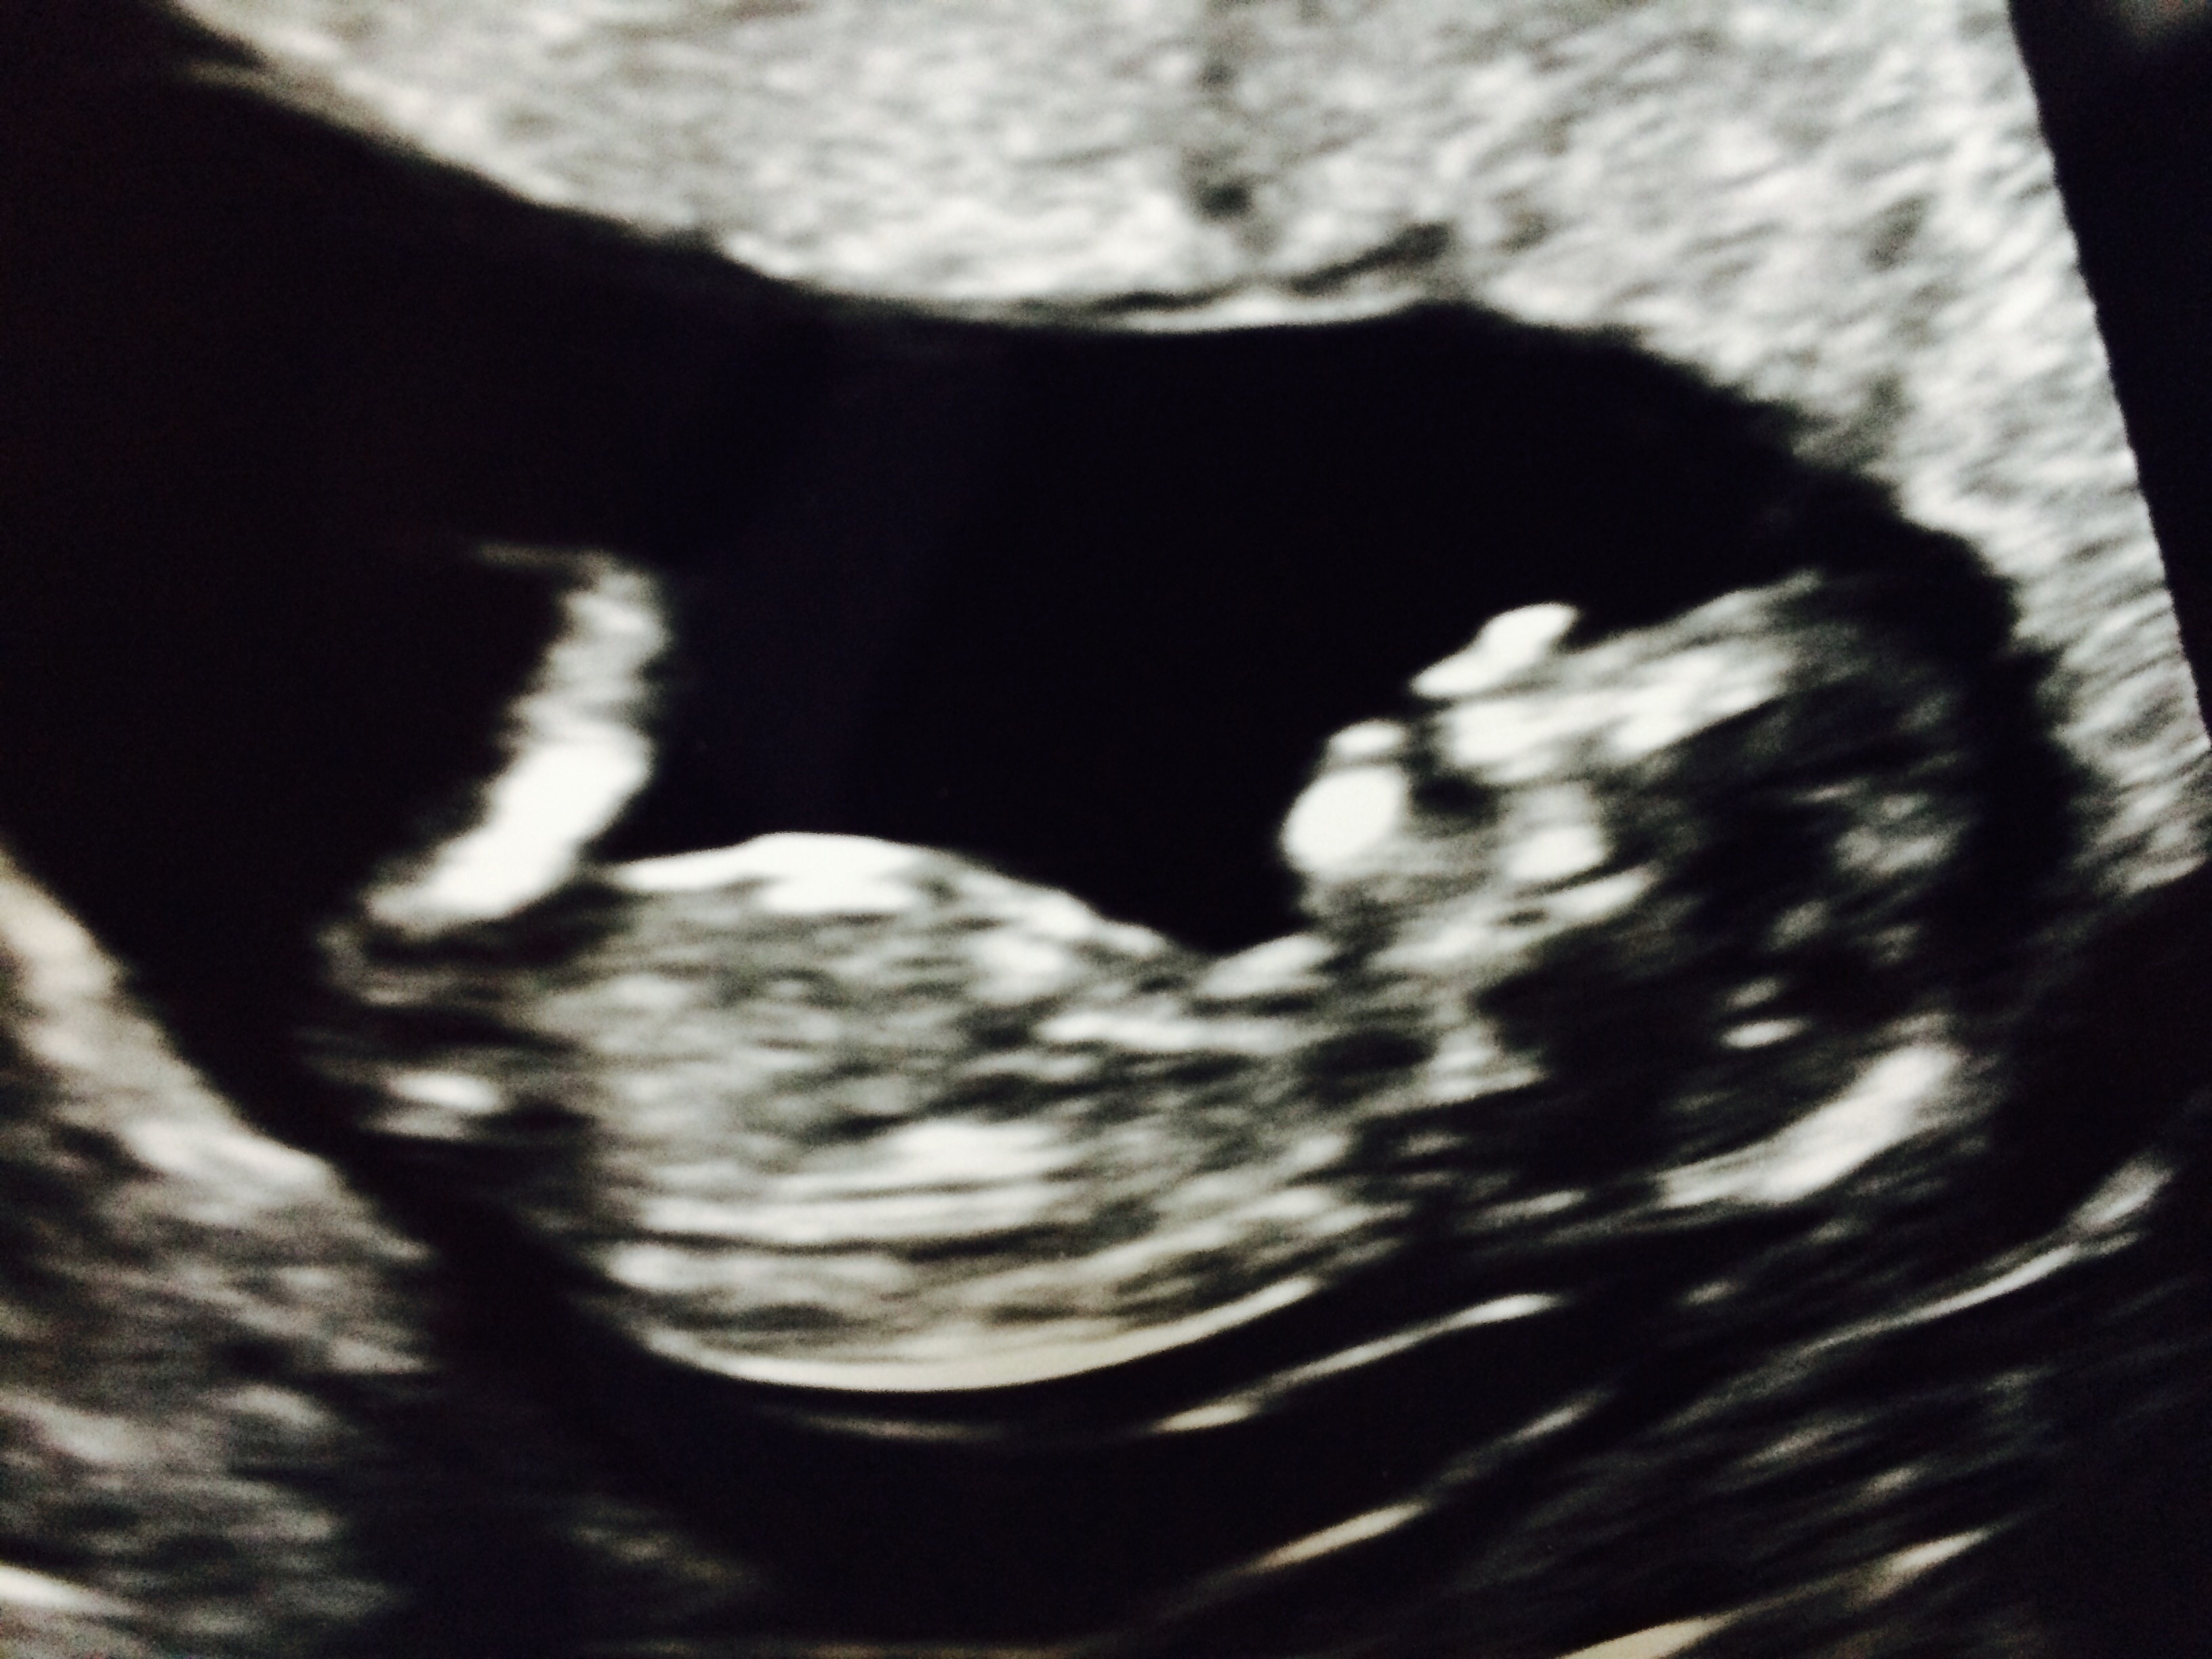

We got the ultrasound on Monday, when I was 9 weeks 3 days. Our doctor told me that I'm measuring slightly bigger, maybe 10 weeks, but it's too early to tell. Lots of wiggling happening and everything looks healthy so far!

We go back on October 5th for the next ultrasound (I'll be roughly 11.5 weeks).